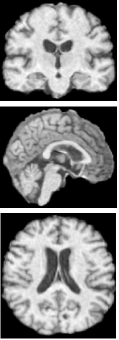

This study uses three publicly available datasets: the National Alzheimer’s Coordinating Center (NACC) [37], the Alzheimer’s Disease Neuroimaging Initiative (ADNI) [38], and the Australian Imaging, Biomarkers, and Lifestyle (AIBL) Study [39]. Each dataset contains 3D MRI scans categorized as NC, MCI, and AD. To ensure uniformity across sources, all MRI volumes are processed using a standardized preprocessing pipeline as described in [40], which involves registration to the MNI152 template for anatomical alignment, skull stripping to remove non-brain tissue, and bias field correction to address intensity inhomogeneity. Demographic information and class distributions for each dataset are summarized in Table 1.